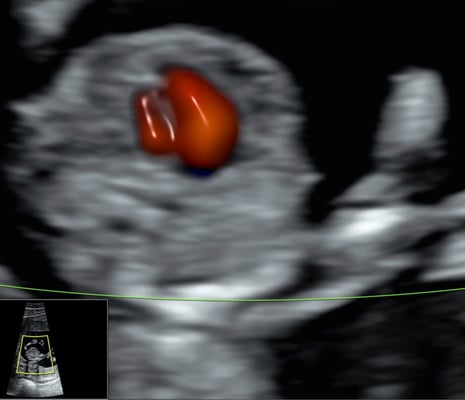

Im Rahmen des traditionellen Dopplersymposiums in Salzburg, welches heuer von 28. bis 30. April 2023 stattfindet, wird in diesem Jahr erstmals ein Fokustag in fetaler Echokardiographie am Samstag, 29. April 2023, angeboten.

Ziel dieser Veranstaltung ist es, innerhalb eines Tages einen umfassenden Einblick in das fetale Herz zu bekommen. Von der Embryologie zur sonographischen Darstellung der normalen Entwicklung, von der Genetik zur sonographischen Erkennung fetaler Herzfehlbildungen, von der Indikation für fetale Echokardiographie zur Indikation pränataler Intervention bei Vorliegen spezieller Herzfehler. Renommierte ExpertInnen mit langjähriger Erfahrung berichten aus ihrer täglichen Arbeit in Praxis- und Klinikalltag. Die KursteilnehmerInnen bekommen im Rahmen von Hands-on-Übungen die Möglichkeit unter Supervision die Standardeinstellungen der fetalen Echokardiographie an Schwangeren im 2. und 3. Trimenon zu erlernen.